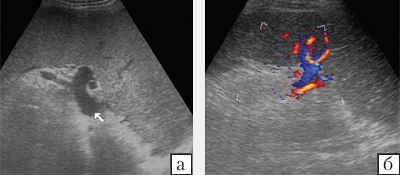

Тромбоз Фото Узи

Тромбоз Фото Узи 115 фотографий